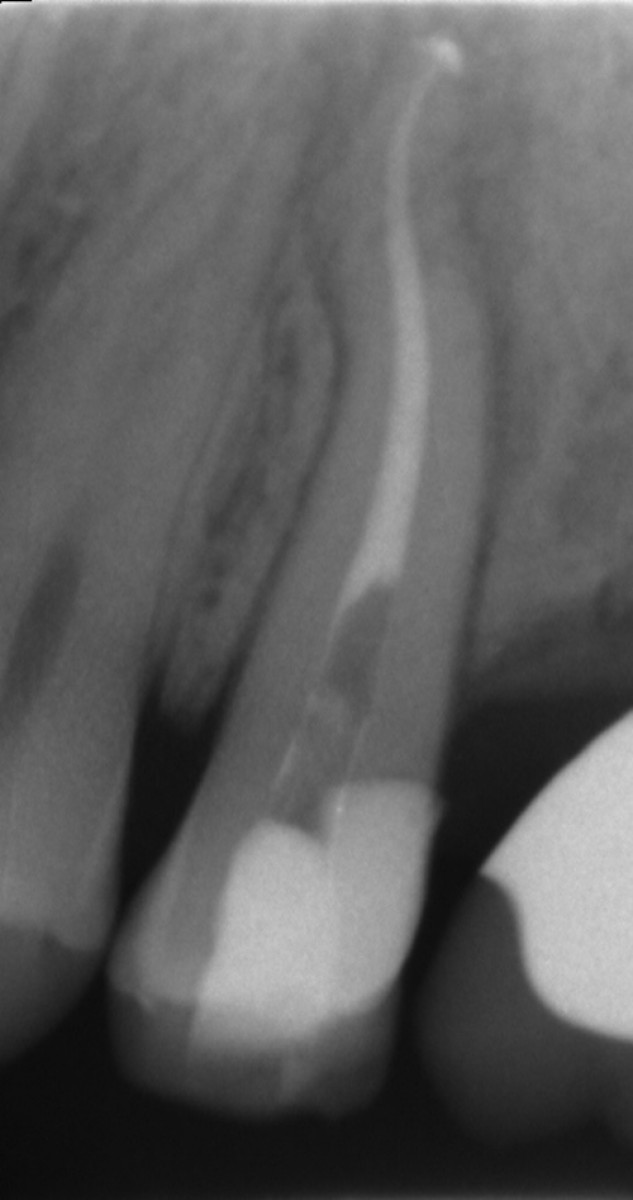

Heat treated Niti Alloys and modern Endodontics Dentistry33

From www.dentistry33.com

Heat treated Niti Alloys and modern Endodontics Dentistry33 Ni Ti Alloy In Dentistry This review aims to provide an overview of nitinol alloys used in dentistry in order for its unique characteristics to be appreciated. Compared the tribological resistance of niti alloy to pure ti and ni and found it to be, respectively, 30 times (ti) and 10 times (ni). In modern orthodontics, the choice of materials plays a significant role in achieving. Ni Ti Alloy In Dentistry.

Heat treated Niti Alloys and modern Endodontics Dentistry33 Ni Ti Alloy In Dentistry An overview of niti shape memory alloy: Firstly, the niti applications in dentistry like orthodontic wires as well as endodontic fields are presented. Compared the tribological resistance of niti alloy to pure ti and ni and found it to be, respectively, 30 times (ti) and 10 times (ni). Corrosion resistance and antibacterial inhibition for dental application. This review aims to. Ni Ti Alloy In Dentistry.

Heat treated Niti Alloys and modern Endodontics Dentistry33 Ni Ti Alloy In Dentistry An overview of niti shape memory alloy: Compared the tribological resistance of niti alloy to pure ti and ni and found it to be, respectively, 30 times (ti) and 10 times (ni). In modern orthodontics, the choice of materials plays a significant role in achieving optimal outcomes. This review aims to provide an overview of nitinol alloys used in dentistry. Ni Ti Alloy In Dentistry.

Heat treated Niti Alloys and modern Endodontics Dentistry33 Ni Ti Alloy In Dentistry Compared the tribological resistance of niti alloy to pure ti and ni and found it to be, respectively, 30 times (ti) and 10 times (ni). An overview of niti shape memory alloy: Firstly, the niti applications in dentistry like orthodontic wires as well as endodontic fields are presented. Corrosion resistance and antibacterial inhibition for dental application. In modern orthodontics, the. Ni Ti Alloy In Dentistry.